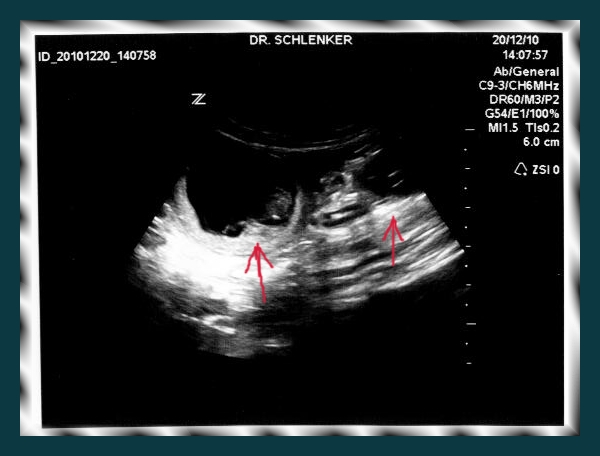

Ultraschallbild Daima H-Wurf